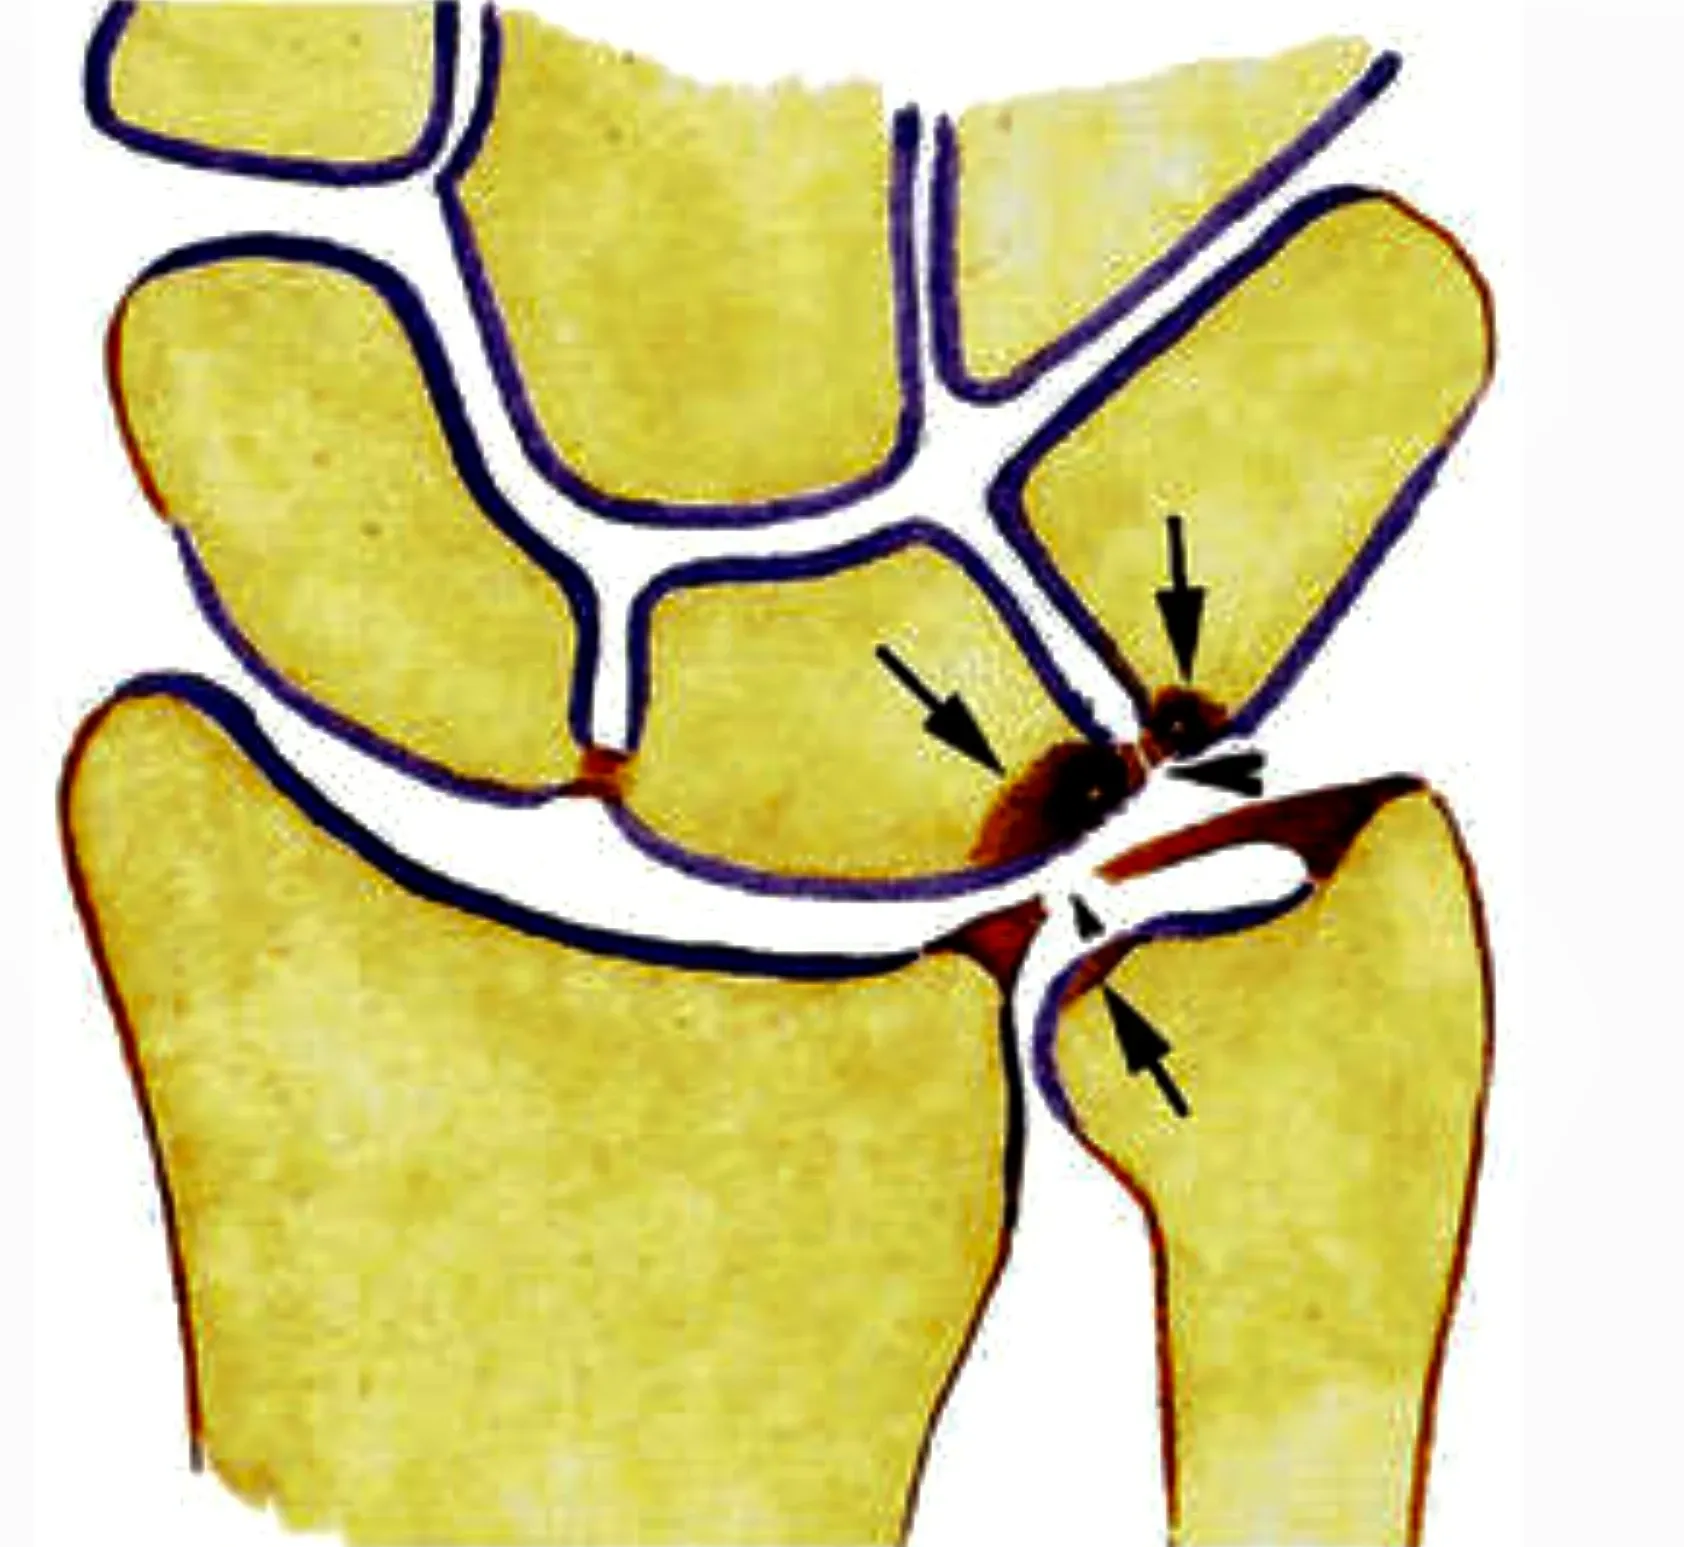

TFCC-letsel

Wat is het?

Het Triangular Fibrocartilage Complex (TFCC) is een soort meniscus van de pols. Het werkt als schokdemper tussen de onderarm en de polsbeentjes en bevat belangrijke stabiliserende ligamenten. Een TFCC-letsel kan ontstaan door:

- een val of plotse draaibeweging

- slijtage, o.a. door langdurige overdruk zoals bij een ulnair impactiesyndroom